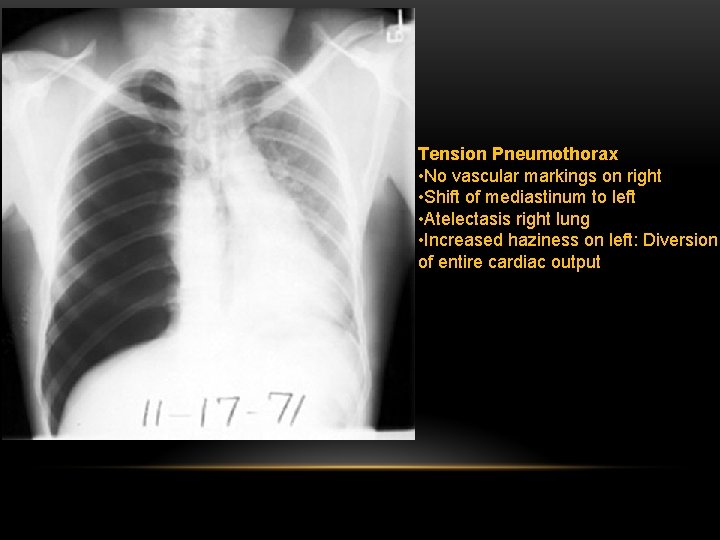

Shift of mediastinum to the opposite side. The mediastinum is held in the middle by balance between pleural pressures. When the negative pressure on the side of the pneumothorax is lost, the mediastinum gets pulled by the normal negative pressure from the opposite side. Progressive shift subsequently could result from a push secondary to tension pneumothorax. Opposite lung gets the entire cardiac output and the vascular markings become prominent.

Tension pneumothorax : is the progressive build-up of air within the pleural space, usually due to a lung laceration which allows air to escape into the pleural space but not to return. Positive pressure ventilation may exacerbate this 'one-way-valve' effect. Progressive build-up of pressure in the pleural space pushes the mediastinum to the opposite hemithorax, and obstructs venous return to the heart. This leads to circulatory instability and may result in traumatic arrest.

Tension Pneumothorax • No vascular markings on right • Shift of mediastinum to left • Atelectasis right lung • Increased haziness on left: Diversion of entire cardiac output